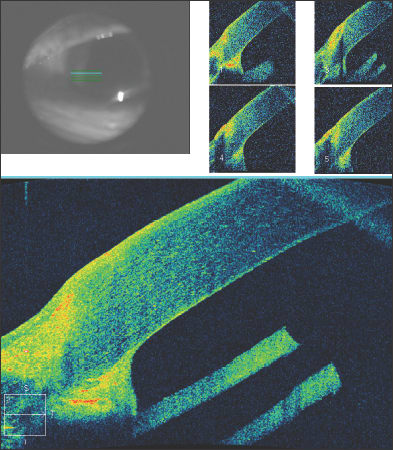

The results of surgical interventions can also be documented, including the position of Descemet's stripping endothelial keratoplasty buttons, glaucoma tube shunts or intraocular lenses. After penetrating keratoplasty, the graft-host interface can be evaluated as seen in this patient with a traumatic corneal laceration, resulting in an emergent penetrating keratoplasty and suboptimal graft-host alignment (Figure 7). Filtering blebs after trabeculectomy can be evaluated, and subconjunctival filtration can be demonstrated (Figure 8).

Figure 7. An irregular graft-host interface following penetrating keratoplasty.

Figure 8. A filtering bleb following trabeculectomy. Fluid is present beneath the conjunctiva and Tenon's fascia.

After DSEK, the position and apposition of the donor endothelial button can be evaluated. In Figure 9a, the endothelial button can be seen to be non-adherent to the corneal stroma, with associated epithelial bullae. After several months, the endothelial button has become fully adherent, and the epithelial fluid has resolved (Figure 9b). In Figure 10, we see a patient who has undergone combined penetrating keratoplasty and tube shunt implantation, and the tube position, while somewhat anterior, is confirmed to be free of corneal touch. The graft-host junction is visualized and the corneal stroma and endothelium anterior to the tube tip appear normal.

Figure 9. Shortly following Descemet's stripping endothelial keratoplasty, the endothelial button can be seen to be non-adherent to the corneal stroma, with associated epithelial bullae (Fig. 9a, above). After several months, the endothelial button has become fully adherent, and the epithelial fluid has resolved (Fig. 9b, below).

Figure 10. Anterior segment OCT of a patient who has undergone combined penetrating keratoplasty and tube shunt implantation. The tube position, while somewhat anterior, is confirmed to be free of corneal touch.